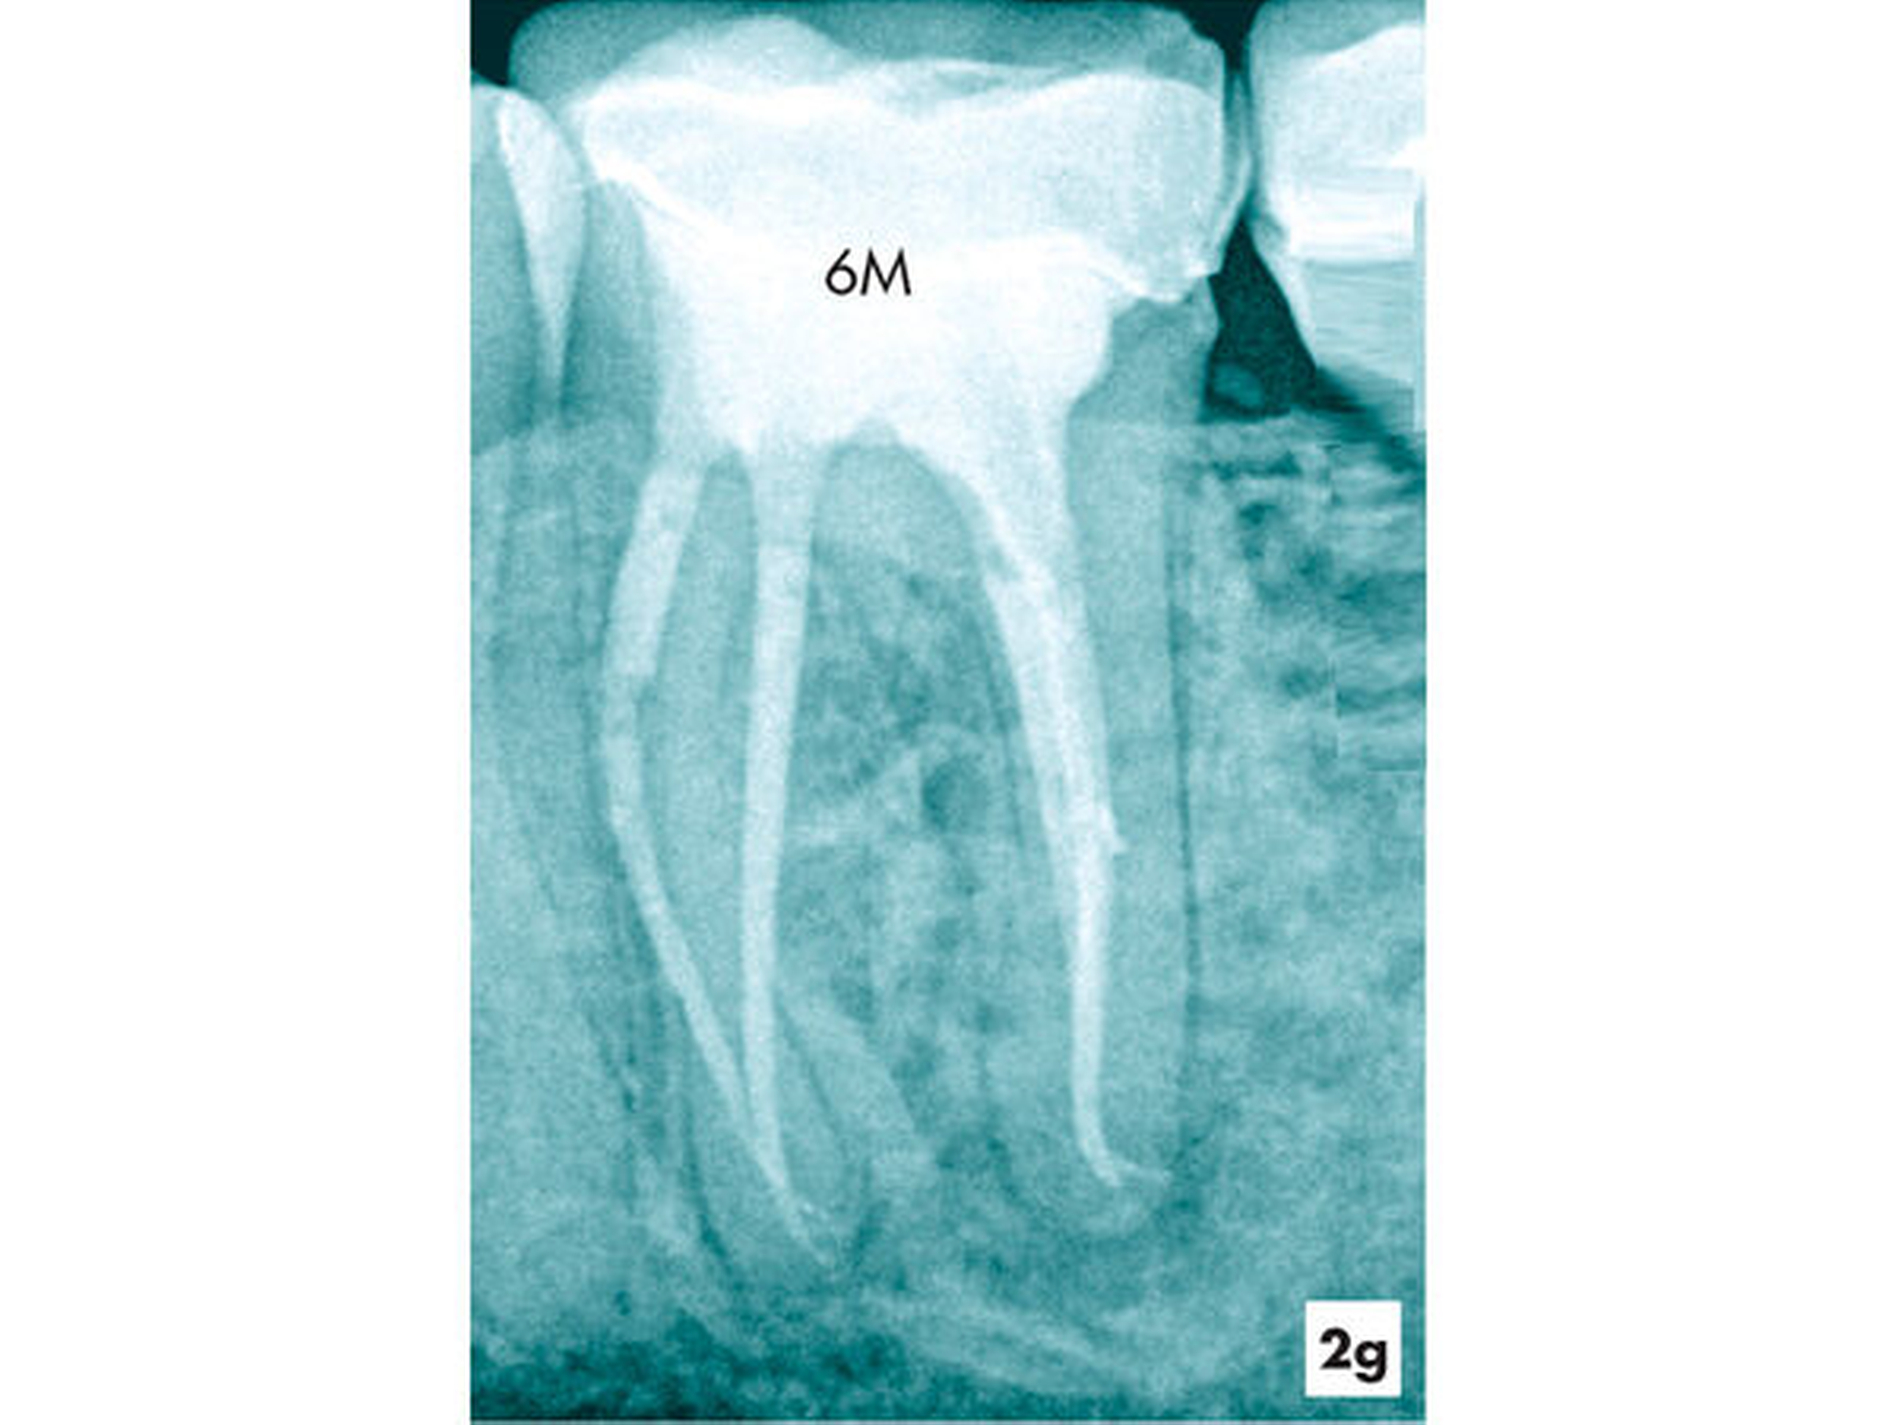

Zwei Tage nach Abschluss der einzeitigen Therapie war die Fistel verschlossen und zum 6-Monats-Recall ließ sich bereits eine deutliche Verringerung der periapikalen Aufhellung nachweisen (Abbildungen 2f und 2g).